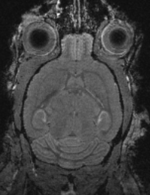

shown are, from left to right, panels of axial, sagittal and coronal views.

original unregistered brains original, not registered

affine registered brains affine registered